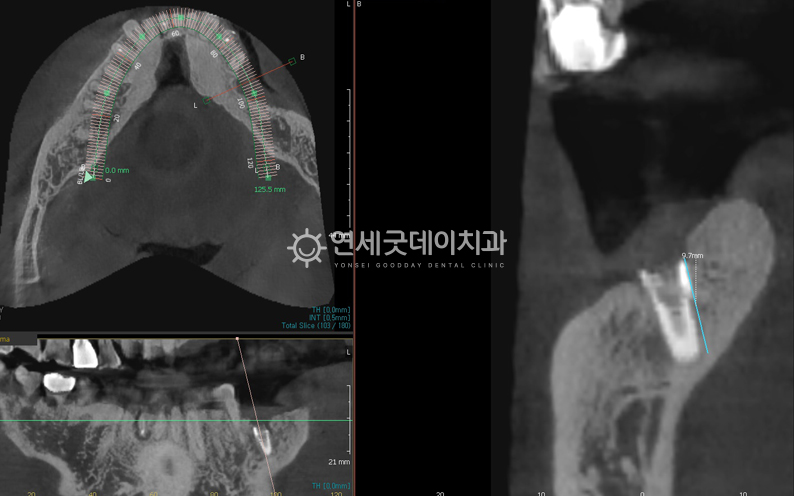

3D 프로그램을 이용해 임플란트와 하치조신경관의 환자분의 경우 임플란트 하단부와 하치조신경관 사이의

제거하기 위험한 케이스였음에도 CT분석을 통해